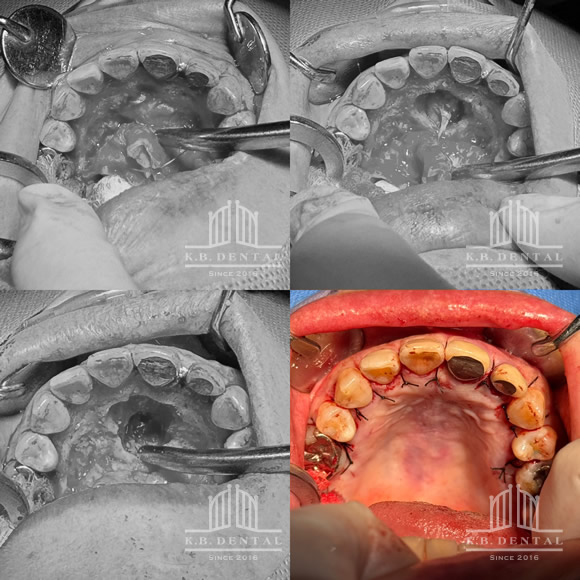

口蓋隆起 症例5(口蓋隆起形成術)

無痛治療での口蓋隆起形成術。骨ノミとピエゾサージェリーを使い、低侵襲な手術を行いました。上顎の違和感がなくなります。

口蓋隆起 症例6(口蓋隆起形成術+親知らず抜歯)

無痛治療で口蓋隆起形成術。同時に左上の親知らずも抜歯しました。ピエゾサージェリーも使い低侵襲な手術を行いました。上顎の違和感がなくなります。